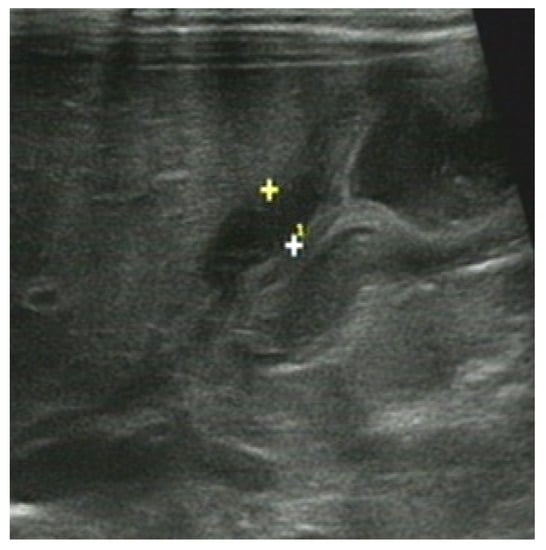

3.2.2. The Corresponding Ultrasound Findings of Diseases Leading to Neonatal Ileus